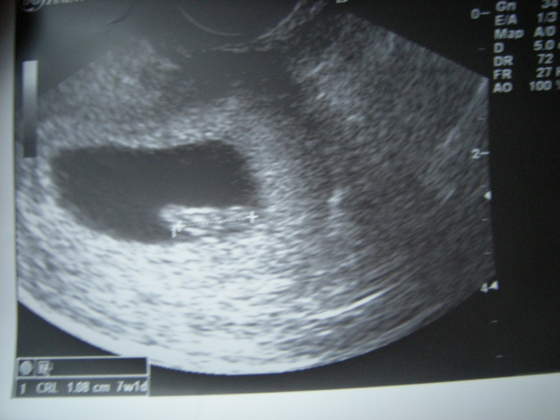

usg.jpg

Moje pierwsze, zrobione 2 tygodnie temu. Dziś myślę, że będzie kolejne :)